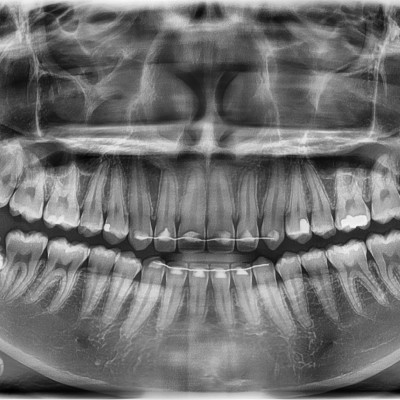

#38 사랑니 발치 구강 외과 전문의가 당일 발치했습니다. #38 사랑니 발치 구강 외과 전문의가 당일 발치했습니다. -----------------------------..

작성자 이턱이 작성일 03-12 조회 43